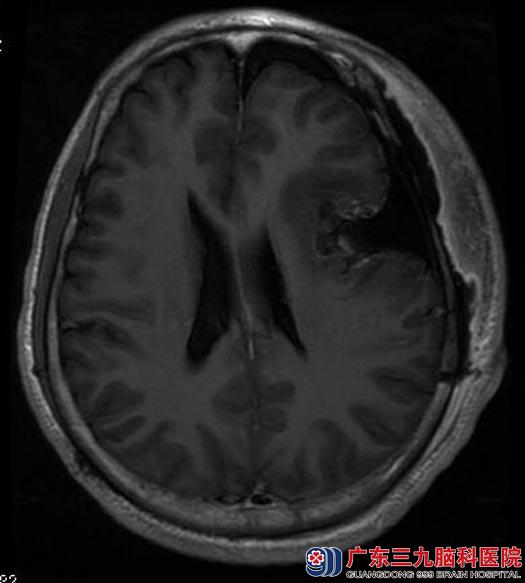

十天前李先生感觉反应明显迟钝,记忆力减退也较之前加重,当地医院查头颅MRI阅片示:左额颞占位性病变,低密度,病灶周围无明显水肿。

广东三九脑科医院进一步头颅MR检查提示:左侧额颞部占位性病变,大小约5.2cm×6.9cm×6.5cm,考虑脑膜瘤。